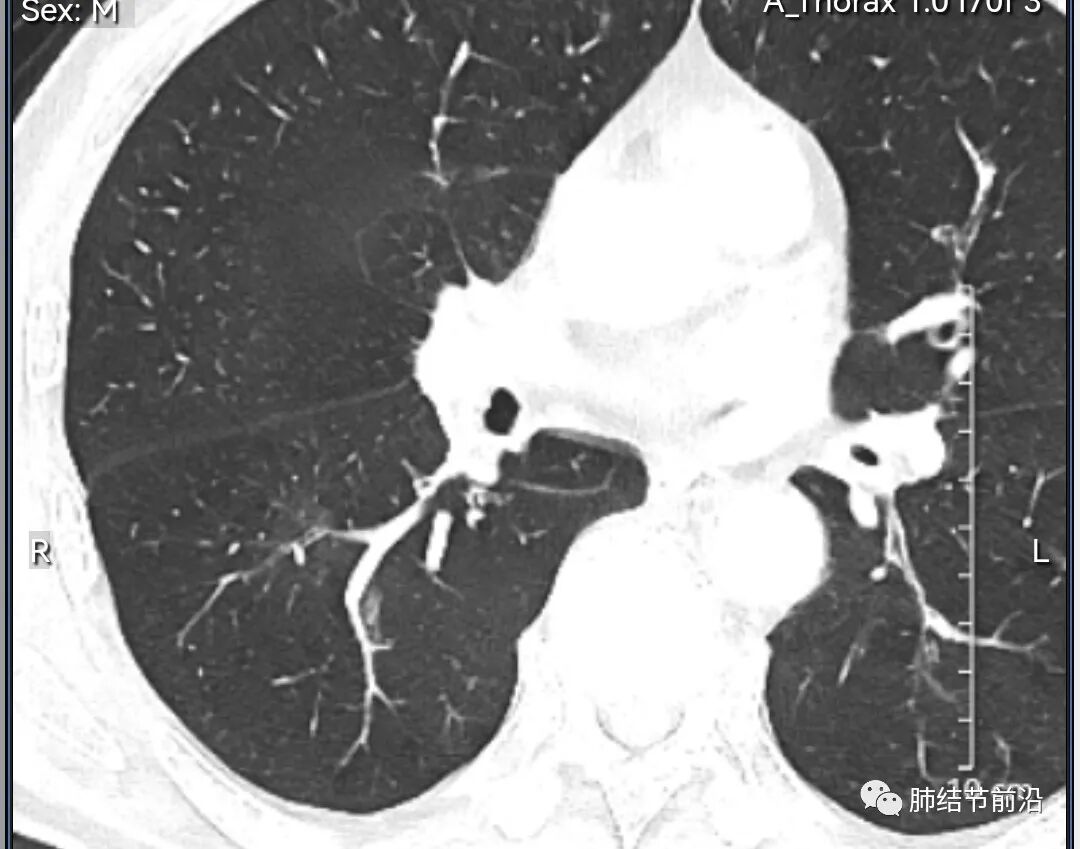

男性,67岁,重度吸烟史。CT发现右下肺囊腔。来看一下这个CT的特点:

该囊腔形态非常有特点,和常见的圆形肺大泡有很大的区别。

1.囊腔中央实性成分,周围有磨玻璃影。

2.囊腔中央有血管。

3.囊腔外周有分叶形态。

4.囊腔有胸膜牵拉。

出现这几种形态,CT可以确认恶性的腺癌。这个囊腔形成的机制,为肿瘤实性成分堵塞细支气管形成活瓣,肺泡内压力增高破裂行成,因此肺内血管成分保留。由于肺泡压力增高,而呈分叶状。另外,也有肿瘤的胸膜牵拉这一特点。

囊腔周围磨玻璃+囊腔中央血管为特征性表现。如果持续存在,几乎可以100%确认为早期肺腺癌。

建议患者手术切除,术后病理为浸润性腺癌,腺泡型,部分为实体型。IA1期,术后不用治疗。